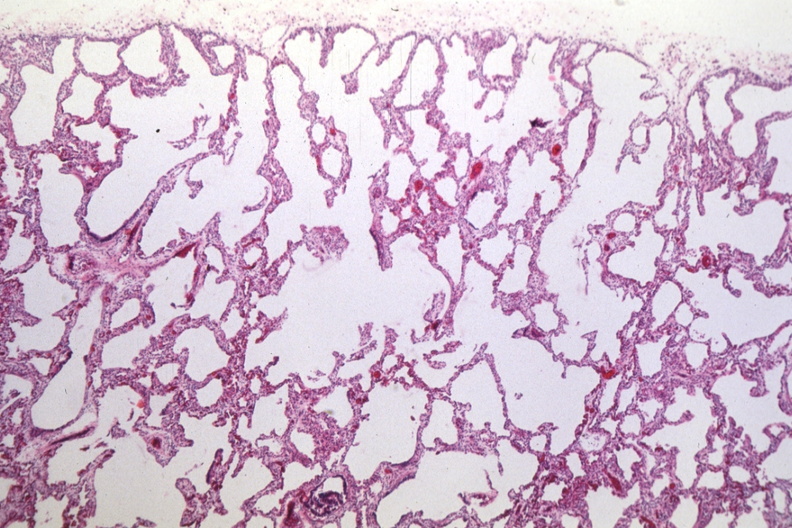

HISTOLOGY: RESPIRATORY: Lung: Interstitial Fibrosis And Emphysema Premature Newborn: Micro low mag H&E 3 mo old child respiratory distress and ventilator entire life

- copd, emphysema, histology, interstitial fibrosis and emphysema premature newborn, lung, respiratory